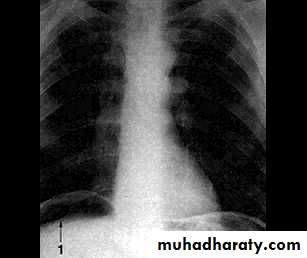

1- Perforation